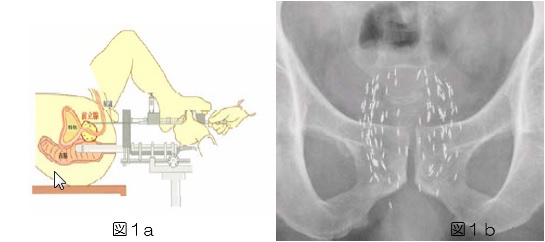

図1aに示すように会陰部(陰嚢と肛門の間)から、X線と超音波を見ながら小線源の挿入を行ないますが、麻酔により疼痛はありません。

前立腺癌に対する放射線治療はその照射方法によって大きく二つに分類されます。ひとつは従来行われてきたように体外から照射を行う外照射法(リニアックなど)であり、もうひとつは小線源治療のように体内から照射を行う内照射法です。この小線源治療は前立腺の内部や近傍へ放射性 物質(小線源)を挿入して、それが放出する放射線により正確かつ的確に立腺への照射を行う方法です。図1aに示すように会陰部(陰嚢と肛門の間)から、X線と超音波を見ながら小線源の挿入を行ないますが、麻酔により疼痛はありません。

挿入後のX線写真を図1bに示します。 通常50~80個程度の小線源を挿入します。